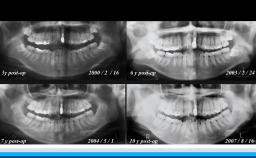

インプラントはQOLと全身の健康状態を向上させる選択肢である

高齢者の咬合力回復は,栄養摂取や全身の筋力維持に貢献できる.インプラント治療もQOL向上に大きく寄与できる可能性を有する.一方,術後の全身の健康状態の変化に対応したメンテナンスを術前から考える必要がある.